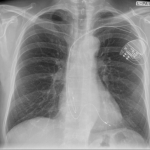

A 58 year old man presents with syncope. LV function is normal.

What is the rhythm?